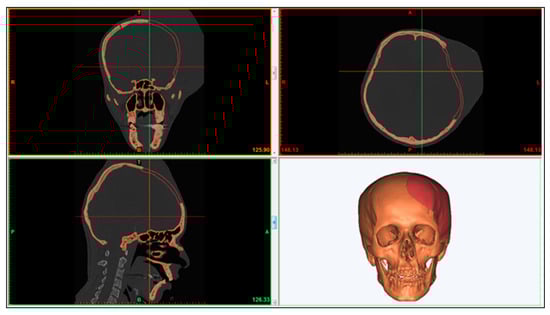

The results obtained after executing the FEA model can be realized in Figure 8. The Von Mises stress distribution is shown in Figure 8a and the maximum value was around 2.5 MPa which was well below the Yield strength (930 MPa) of the titanium alloy (Ti6Al4V ELI) thus ensuring the absence of any plastic deformation in the implant. Moreover, the maximum principal strain distributions in Figure 8b marked comparatively high strained regions around fasteners and load areas. However, the overall strain levels were very low and the maximum value was around 1.49 × 10−4. Similarly, Figure 8c shows the deformation pattern in the implant due to the applied load. As expected, maximum deformation occurred at the load area, however, the magnitudes were very low i.e., around 3.26 × 10−6 mm. In conclusion, the results showed that the implant design could be used satisfactorily for the replacement of the defected skull region.

Figure 8. FEA Results illustrating: (a) stress distribution; (b) strain distribution; (c) maximum displacement.